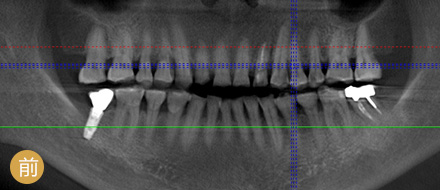

数字化精确导航种植

导航辅助种牙,创口小更舒服

VS 传统种植牙 全数字化精确种牙

手术时间 平均1颗牙1小时 单颗牙5~10分钟

恢复周期 拔牙后3个月修养,需二次种植 即拔即种,即种即用

准确程度 依赖医生个人判断种植角度 外科导航系统定位,实时监控,避开血管神经

安全性 医生个人经验决定了种牙效果 神经、血管可见,导航全程定位,

种牙效果稳定可靠

功能行使 愈合周期略久,较难参与日常咀嚼 种牙后即可马上使用

操作医生 普通种植医生 麦芽博士级专家团队

手术创伤 一般要翻瓣缝合,不适感较强

体质差的人易感染与红肿

3毫米创口,精确植入牙骨

不翻瓣不缝合,术后基本无肿胀期